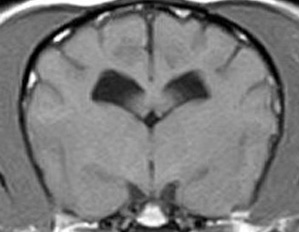

5~6歳以上の去勢手術をしていないオス犬に多い病気ですが、メス犬や去勢した犬に起こることもあります。お尻の筋肉が萎縮した結果、筋肉の隙間から直腸や膀胱が皮膚の下にとびでてしまいます。これにより便が出にくくなったり膀胱炎になったりします。手術をすることで機能回復および今後の致死的な状況を回避することができます。当院では去勢手術→結腸固定→前立腺固定→骨盤隔膜構成筋の縫縮→内閉鎖筋フラップ→浅臀筋フラップの順で通常腹側・臀部左右両側同時に行います。また老化以外に、筋肉が萎縮する原因があったり、腹圧がかかる原因があったりする場合も多いので、再発防止のためそれらの診断・治療も重要です。今回のワンちゃんも無事手術も終わり元気に退院しました。よかったね。